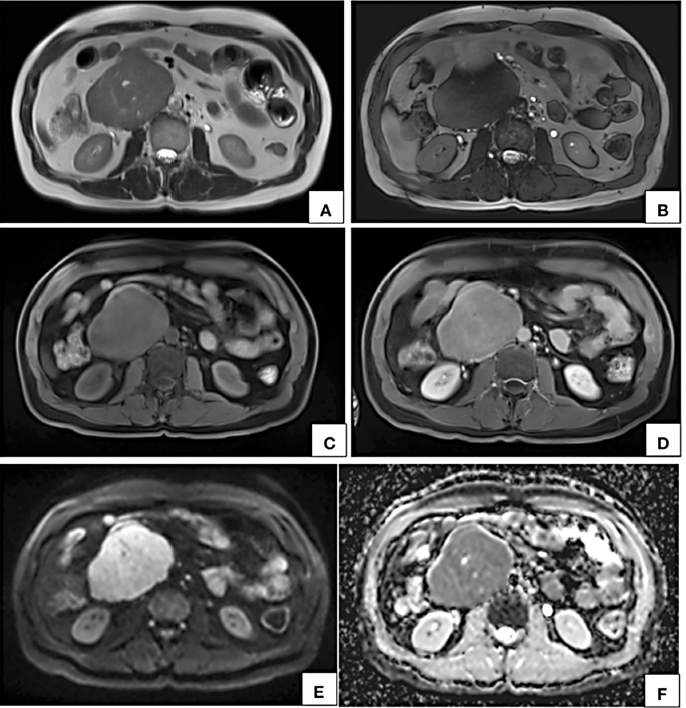

lumen at the site of maximum contact. However, proximal and distal segments of the inferior vena cava showed normal contrast opacification. Medially, the lesion was in relation to the abdominal aorta. Second and third part of duodenum and head of pancreas were displaced anterosuperiorly. Magnetic resonance imaging (MRI) showed a homogeneously enhancing circumscribed lesion in the retroperitoneum on right side of midline appearing isointense on T1W, hyperintense on T2W showing restricted diffusion. Few cystic areas were seen within the lesion. On prone imaging, the lumen of inferior vena cava was still imperceptible at the site of maximum contact. No obvious intraluminal extension was seen. Whole body positron emission tomography CT revealed mild FDG uptake with a maximum standard uptake value (SUVmax) of 4.1. No distant metastases were found.

On MR imaging LMS of IVC appears hypo- to intermediately intense on T1W and hyperintense on T2W [10, 18, 26]. Due to their malignant nature, these tumors also show diffusion restriction [18]. Similar signal characteristics were observed in our case also.